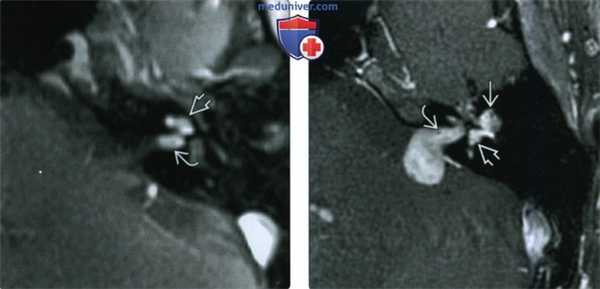

(Слева) При аксиальной МРТ Т1ВИ С+ определяется контрастное усиление дна дистального ВСК и улитки (ИЛШ трансмодиолярного типа). Опухоль растет из улитки через стержень и канала улиткового нерва, достигая дна ВСК.

(Справа) При аксиальной МРТ Т1ВИ С+ визуализируется крайне редкая ИЛШ трансотического типа. Обратите внимание, что опухоль, накапливающая контраст, распространяется через ВСК из ММУ, а также поражает внутреннее и среднее ухо.